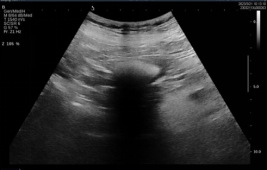

因患者高龄,既往冠心病史多年,有一过性晕厥病史,胃镜诊治危险性高。患者口服PPI及碳酸氢钠,联合口服碳酸饮料治疗溶石,7日后,行胃超声检查评估目前胃石情况。超声所见如下:

image.pngimage.png

3,4  胃腔内见结石强回声,后伴明显声影,长约7cm